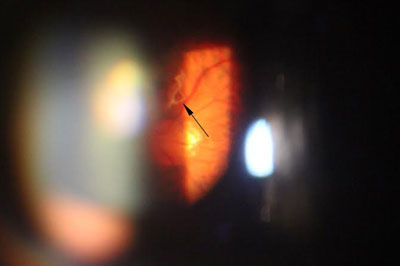

年屆四十至五十歲的病人,出現急症飛蚊大多是由於玻璃體液化以至出現「後玻璃體脫落」,當玻璃體從視神經盤脫離時,往往便出現較大和明顯的玻璃體「殘留物」,而導致嚴重飛蚊症狀,小部份病人亦會出現視網膜裂痕,出血和脫落等併發症,以致危害視力。雖然大部份病人沒有視力嚴重受損的風險,但較嚴重的飛蚊症狀會帶來視覺上的不便。治療此類飛蚊症,一般藥物治療效果有限,而侵入性外科手術 (玻璃體切除) 亦只適合如玻璃體出現嚴重出血或撕裂等併發症患者。

隨著激光技術的發展,近年已發展出激光治療飛蚊症,用於把較大和集中的玻璃體浮游物打散,以達到改善和消除飛蚊症狀,過程約十五至二十分鐘,沒有痛楚,並可於局部麻醉下進行。但並不是所有患有飛蚊症的人均適合做激光治療,如「飛蚊」物質較鬆散或位置太接近黃斑或晶體,便不適合進行此類激光治療,以免導致白內障或黃斑受損等併發症。